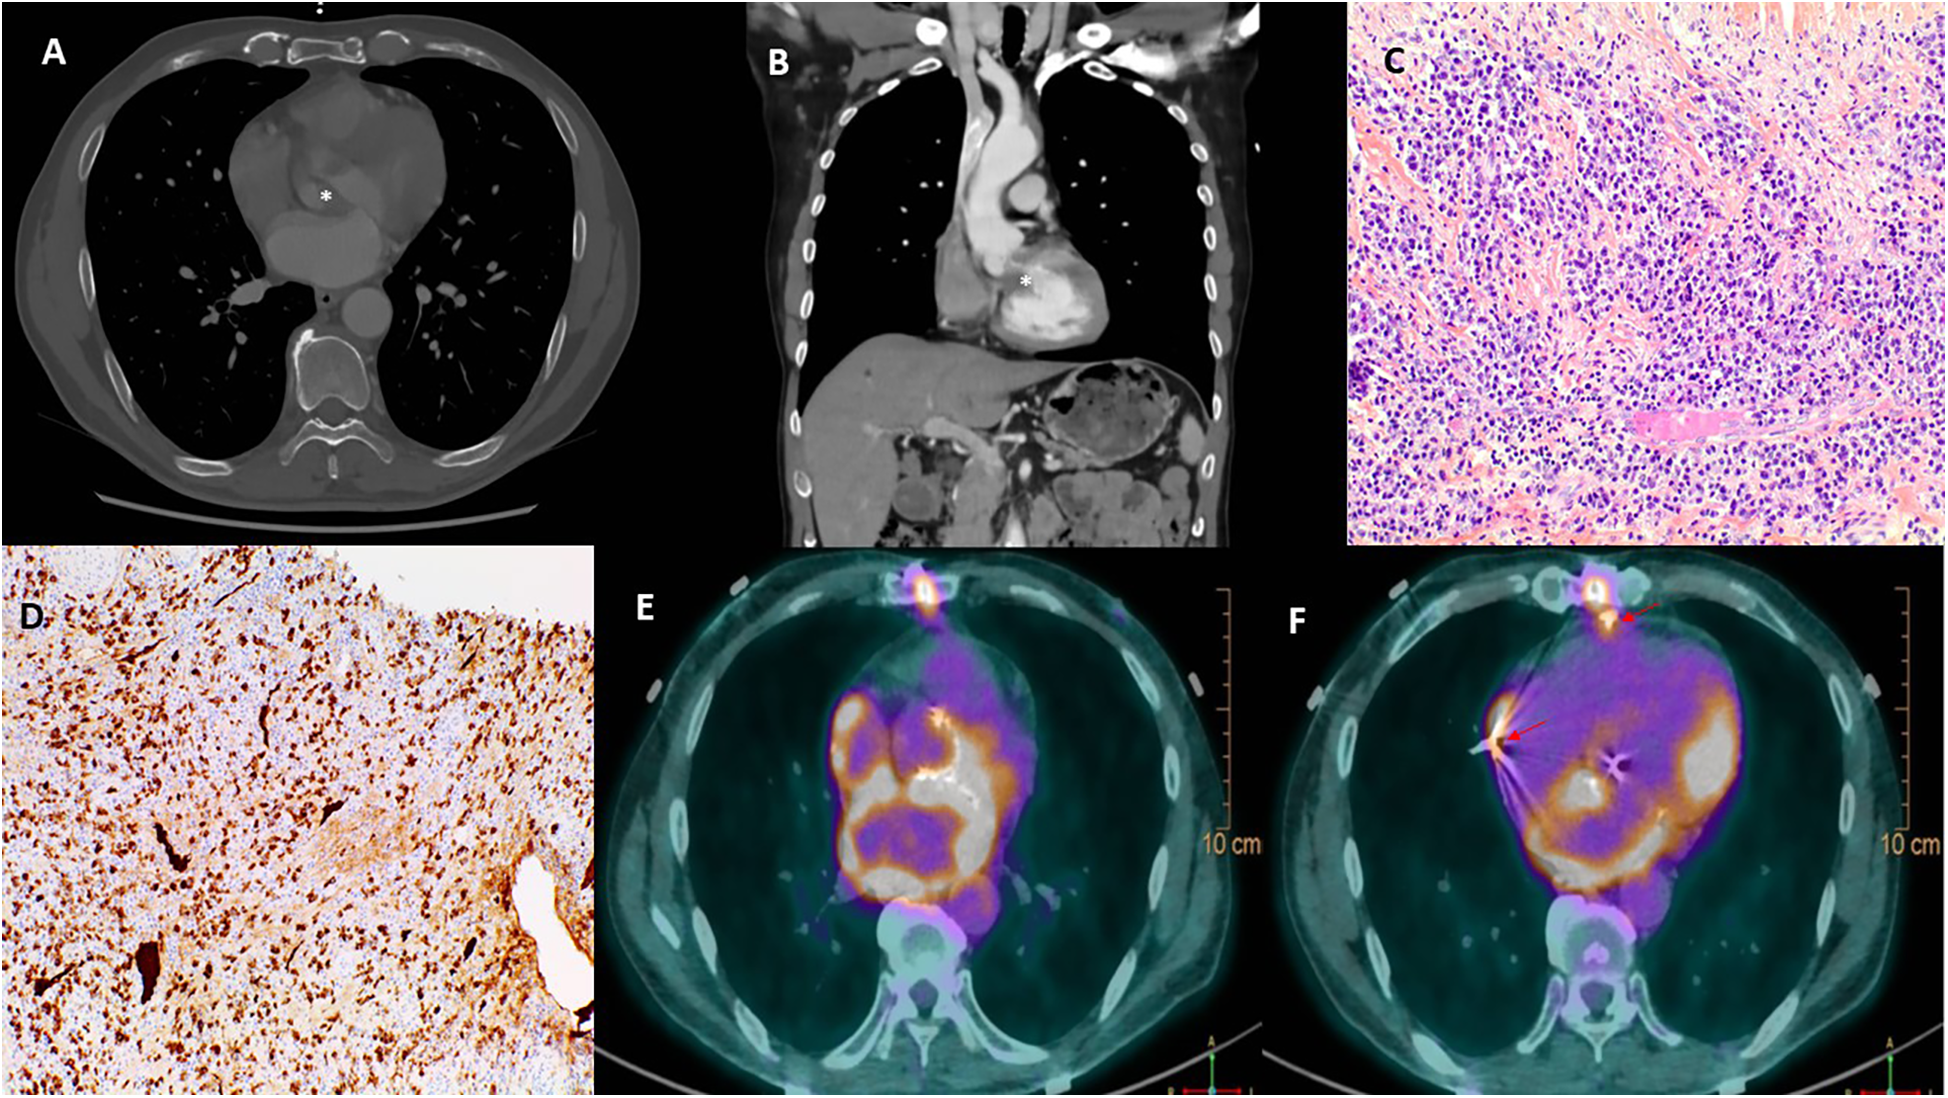

Initial electrocardiogram (ECG) showed sinus rhythm with right bundle branch block and left anterior fascicular block. Holter monitoring revealed paroxysmal complete AVB lasting 8 s. Transthoracic and transesophageal echocardiography revealed preserved left ventricular ejection fraction (LVEF, 68%), moderate aortic regurgitation, and significant thickening of the aortic valve extending to the aorto-mitral curtain and anterior mitral valve (Figures 1A,B), causing LVOT obstruction with maximal and mean gradient of 70 and 44 mmHg (Figure 1C), respectively. Computerized tomography (CT) confirmed hyperplasic tissue at the LVOT (Figures 2A,B). Coronary angiography showed normal results. Laboratory tests showed mild leucocytosis (135 000/ml), slightly elevated C-reactive protein (12 mg/L), and NT-pro brain natriuretic peptide (295 pg/ml); troponin level was normal.

Figure 2

Multimodal images depicting IgG4-RD. Computerized tomography confirmed a significant thickening of the aortic valve (*, A) and an obstruction of the left ventricular outflow tract (*, B). Hematoxylin and eosin stain (C) of resected tissue demonstrated storiform fibrosis and dense inflammatory infiltrate with a majority of lymphocytes and plasma cells. Immunoglobulin G4 immunohistochemical stain (D) showed numerous IgG4+ plasma cells. 18F-Fluorodeoxyglucose positron emission tomography (E,F) demonstrated a hypermetabolism due to a recent surgery in the left atrium, the aortic root, and the sites of epicardial electrodes (arrow, F).

The postoperative course was uneventful, and the patient was discharged on day 10. Echocardiography showed well-functioned aortic and mitral prostheses (Figures 1D–F); electrophysiological control of epicardial electrodes and pacemaker was normal. A pathological examination revealed lymphoplasmacytic infiltration and IgG4+/IgG+ cell ratio of 30%–50% (Figures 2C,D), suggesting IgG4-RD.

Two months later, the patient had another syncopal episode. ECG showed complete AVB and pacemaker dysfunction; PET scan revealed hypermetabolism in the aortic root, left atrium, and epicardial electrode sites, while the interpretation was difficult due to recent surgery (Figures 2E,F). Glucocorticoids (intravenous loading dose of methylprednisolone 750 mg, followed by prednisolone 60 mg/day) were started.